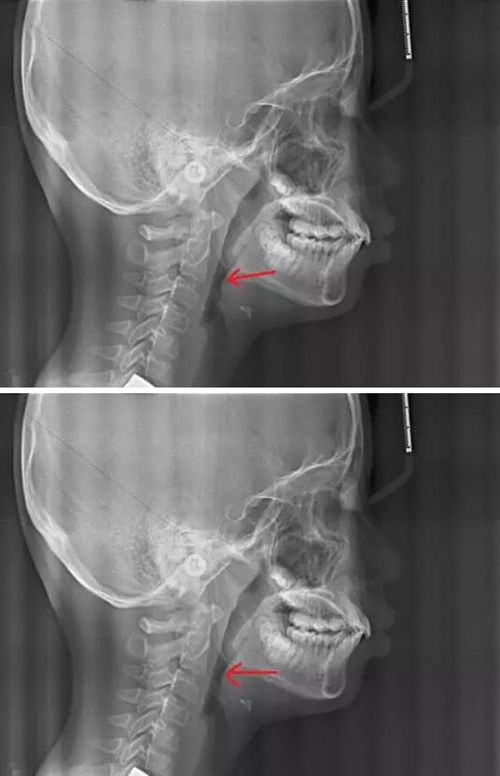

我們再來看兩張肥大的扁桃體

2.jpg